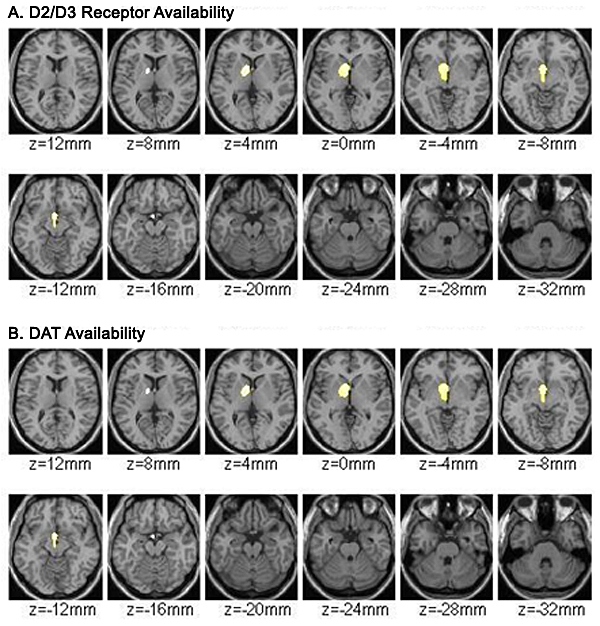

Reduced dopamine receptor availability

Altered dopamine transporter function

Image caption: Brain imaging studies show differences in reward processing between ADHD and non-ADHD brains.